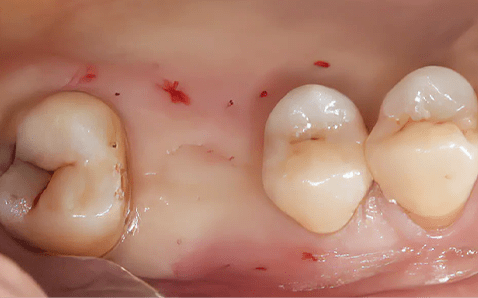

Case 01

Before Implant Placement Right After Flapless Implant Placement

Photo Date : 2024.12.05